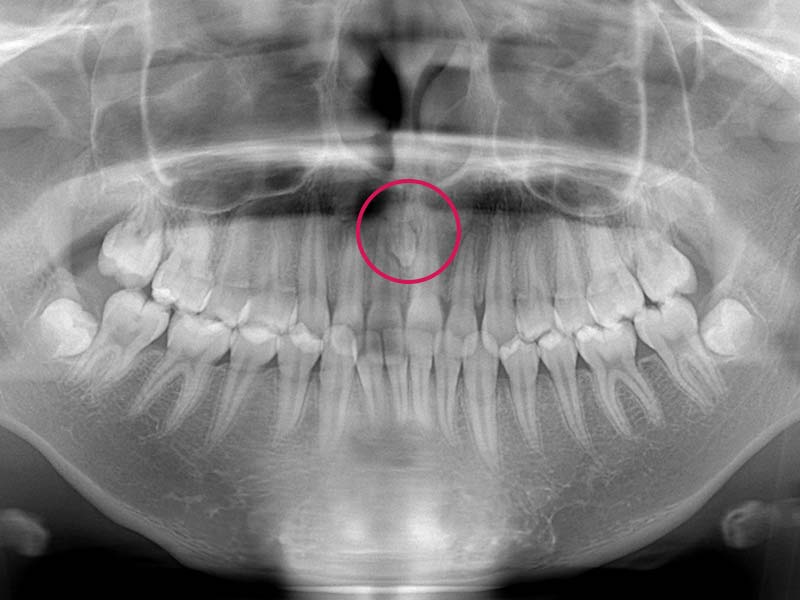

過剰歯

一般的に、永久歯の本数は親知らずを含めると全部で32本あります。これよりも多くの歯がある状態を過剰歯といいます。上の前歯の真ん中に過剰歯が埋まっていると、前歯の真ん中に隙間ができる原因となることがあります。

どうやって治療するの?

まずはレントゲン撮影を行い、過剰歯の有無を確認します。過剰歯がある場合、隙間ができてしまうだけでなく、前歯の根っこに悪い影響を与えてしまうこともあるため、口腔外科にて抜歯していただきます。

先天性欠損や埋伏歯の症状